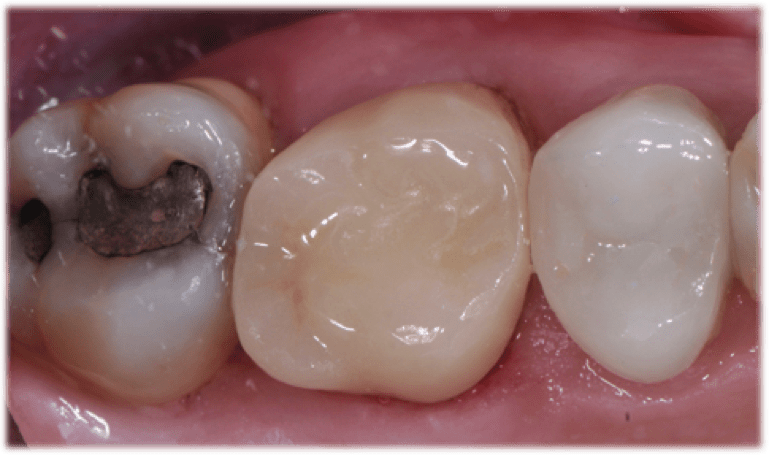

Taking a systematic approach to bur selection will streamline the chairside experience for the practitioner and the patient. In this case, I am prepping tooth No. 3 for a partial coverage restoration. It is a large filling with decay underneath. Whether it is partial (Figure 1) or full (Figure 2) coverage, preparation design should begin with the removal of the existing filling and any decay (Figure 3). This step is usually accomplished with the use of a Solo diamond double inverted cone. Once this step is complete, the clinician should either break contact with a flame or begin occlusal reduction with the football diamond. The preparation may require a build-up material to idealize the shape after the general form has been completed.

The preparation margins are then finished per the dental designer’s preference, which involves using burs and diamonds. The primary goal in bur selection is to choose a dependable, well-made, sterile, and predictable bur that will accomplish the best preparation. I prefer to use a shoulder preparation with a flat end taper, such as the Solo course grit 837012C or 837016C. The 12C and 16C signifies the diameter of the bur and is a useful tool in determining the amount of tooth reduction made on the axial walls. However, different clinical situations may require different burs, so dental designers should not limit themselves to one particular model or line.